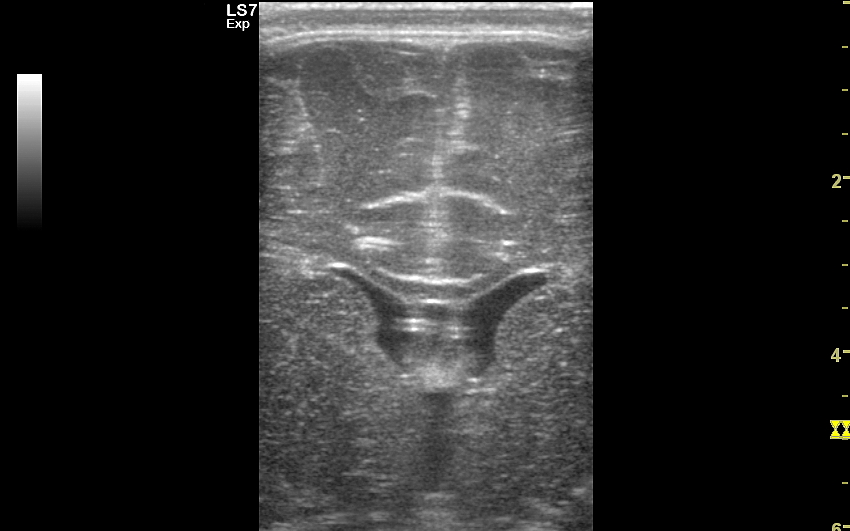

USG główki z oceną szwów i powłok

Poza strukturami wewnątrzczaszkowymi w badaniu USG główki niemowlaka oceniana jest pokrywa czaszki, w tym szwy i kości czaszkowe, tkanka podskórna oraz skóra głowy. Badanie USG szwów czaszkowych ma istotne znaczenie przy ocenie niesymetrycznego lub zdeformowanego kształtu głowy w kontekście rozpoznania kraniosynostozy (ang. craniosynostosis), tj. stanu, w którym dochodzi do przedwczesnego oraz nieprawidłowego zarastania szwów. W kraniosynostozie w miejscu zarastania tworzy się zwykle patologiczne twarde uwypuklenie / guz, które posiada charakterystyczny obraz sonograficzny pozwalający na rozróżnienie zarastania szwów w przebiegu kraniosynostozy od przedawkowania witaminy D, czy fizjologicznej wcześniejszej fuzji kości czaszki.

Patologiczne zarastanie szwów może być symetryczne lub niesymetryczne oraz dotyczyć jednego lub więcej szwów. W zależności od tejże konstelacji czaszka może przyjmować różnorodne formy deformacji w postaci scaphocefalii (syn. dolichocephalia, czaszka łódkowata / wydłużona w przebiegu zarośnięcia szwu strzałkowego), brachycefalii (krótkogłowie w przebiegu zarośnięcia obu szwów wieńcowych)trigonocefalii (trójkątnogłowie w przebiegu zarośnięcia szwu czołowego), plagiocefalii przedniej lub tylnej (skośnogłowie w przebiegu zarośnięcia jednego ze szwów wieńcowego lub węgłowego), turricefalii (syn. oxycefalia, czaszka wieżowata w przebiegu zarośnięcia szwów wieńcowych i któregoś z pozostałych), mikrocefalii (mała czaszka w przebiegu zarośnięcia wszystkich szwów) lub czaszki w kształcie liścia koniczyny (niem. kleeblattschädel). Sprawna diagnostyka deformacji czaszki ma wielkie znaczenie. Otóż kraniosynostoza jest potencjalnie niebezpieczna dla zdrowia, a nawet życia dziecka, a zwykle leczy się ją chirurgicznie. Z kolei częściej występująca łagodna deformacja w postaci plagiocefalii ułożeniowej wywołana jest zwykle tendencją do leżenia dziecka na wznak z główką skierowaną w jedną stronę, zwykle prawą; jest ona problemem bardziej estetycznymi aniżeli medycznym, a leczy się ją przy pomocy kasku oraz zaleceń rehabilitacyjnych.